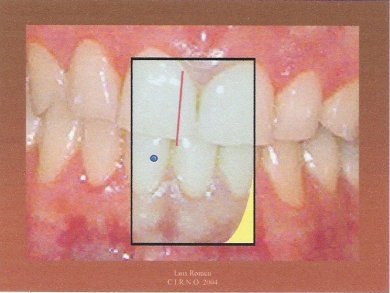

4.- Invitamos al paciente a realizar una lateralidad derecha. Es aconsejable que sea lo más amplia posible siempre y cuando el trayecto sea rectilíneo. Marcamos sobre el papel celo un punto encima del que pintamos en el primer paso.

5.- Repetimos el paso anterior pero lateralizando para la izquierda.